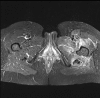

Figure 1

An axial MRI T-2 weighted image with fat-saturation which demonstrates diffuse high signal abnormality in the left anterior, posterior and medial compartments of the thigh (TE 32 ms TR 3500).